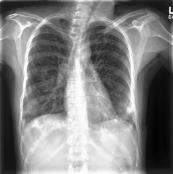

Large numbers of labeled medical images are essential for the accurate detection of anomalies, but manual annotation is labor-intensive and time-consuming. Self-supervised learning (SSL) is a training method to learn data-specific features without manual annotation. Several SSL-based models have been employed in medical image anomaly detection. These SSL methods effectively learn representations in several field-specific images, such as natural and industrial product images. However, owing to the requirement of medical expertise, typical SSL-based models are inefficient in medical image anomaly detection. We present an SSL-based model that enables anatomical structure-based unsupervised anomaly detection (UAD). The model employs the anatomy-aware pasting (AnatPaste) augmentation tool. AnatPaste employs a threshold-based lung segmentation pretext task to create anomalies in normal chest radiographs, which are used for model pretraining. These anomalies are similar to real anomalies and help the model recognize them. We evaluate our model on three opensource chest radiograph datasets. Our model exhibit area under curves (AUC) of 92.1%, 78.7%, and 81.9%, which are the highest among existing UAD models. This is the first SSL model to employ anatomical information as a pretext task. AnatPaste can be applied in various deep learning models and downstream tasks. It can be employed for other modalities by fixing appropriate segmentation. Our code is publicly available at: https://github.com/jun-sato/AnatPaste.